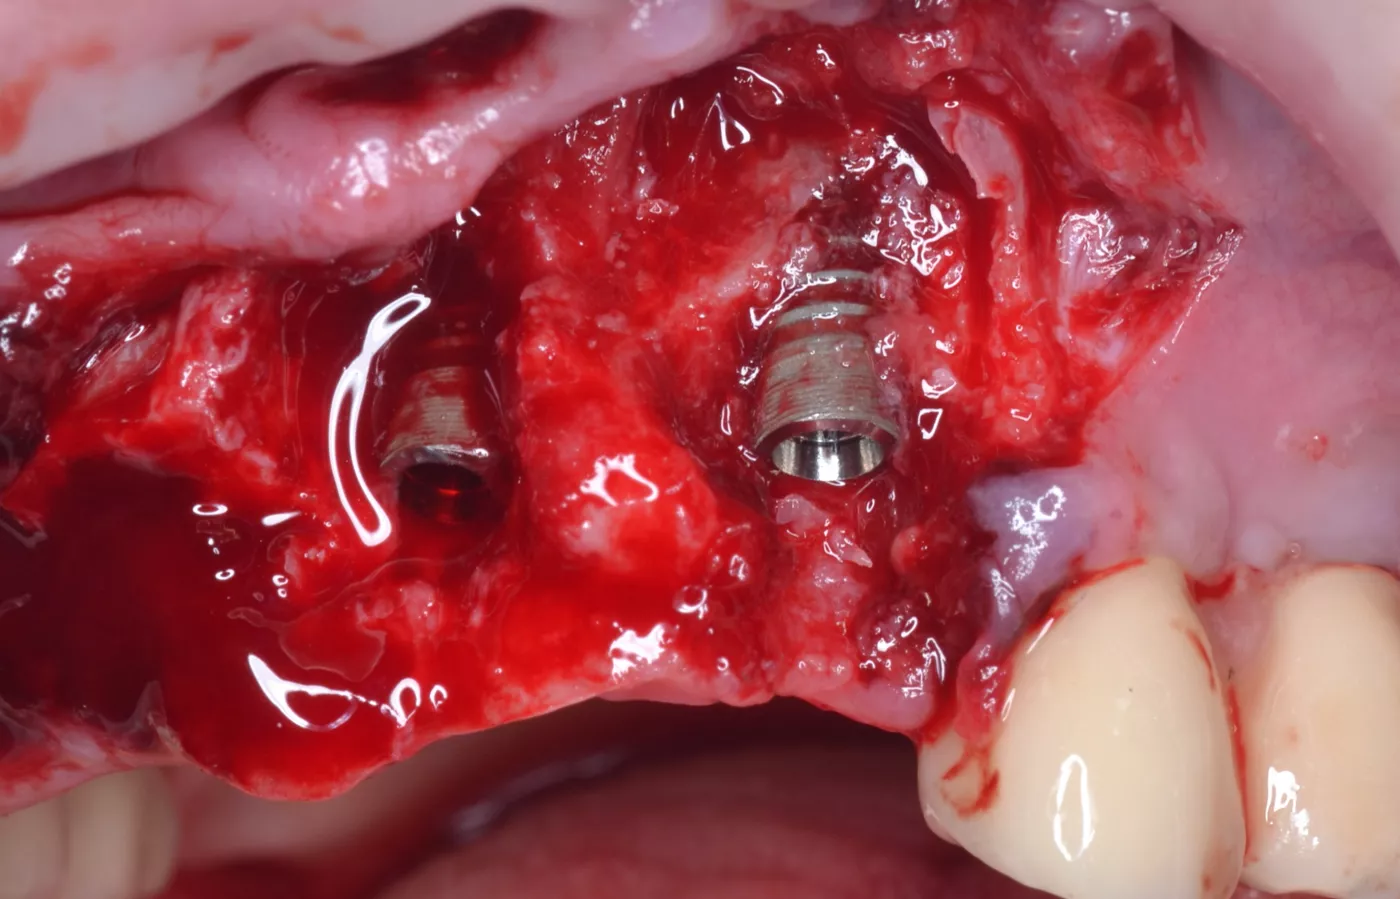

Зафиксирован хирургический шаблон, с помощью которого было подготовлено ложе и установлены имплантаты на нужном заглублении (Илл. 17-18, Видео 1).

После установки имплантатов произведена оценка дефекта вестибулярной стенки в обл. 2.1, 2.3 имплантатов для определения объема реконструкции дефекта (Илл. 19).